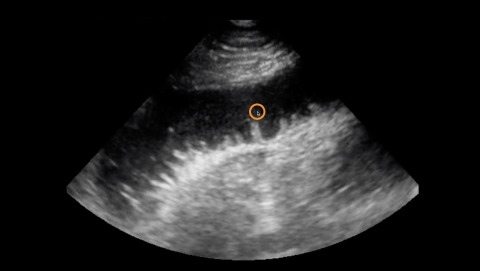

Ultrasound of Small Bowel Obstruction

Jailyn Avila reviews the ultrasound findings of small bowel obstruction.